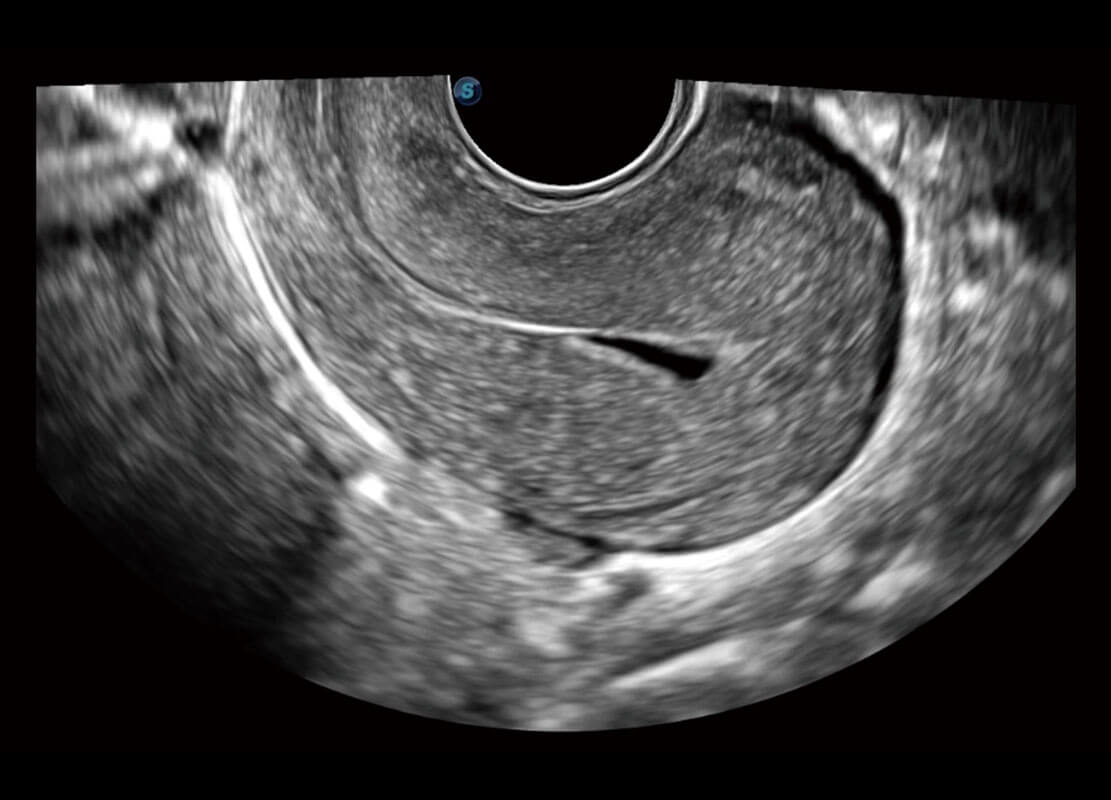

P60優(yōu)異的圖像質(zhì)量搭載專科探頭,在婦科基礎(chǔ)疾病的診斷、卵泡生長(zhǎng)的監(jiān)測(cè)、輸卵管通暢情況的判別等方面為您提供生殖應(yīng)用方案。

腔內(nèi)婦科-卵巢